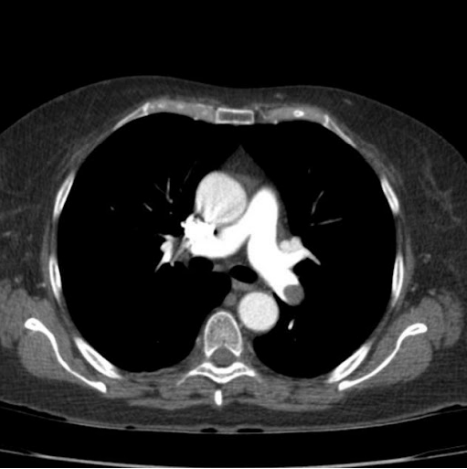

Angiotomografia de Tórax (Angio-TC)

- É o método de escolha para o diagnóstico.

- Apresenta alta sensibilidade (83%) e especificidade (96%).

- Possui alto VPN em pacientes com risco baixo ou intermediário.